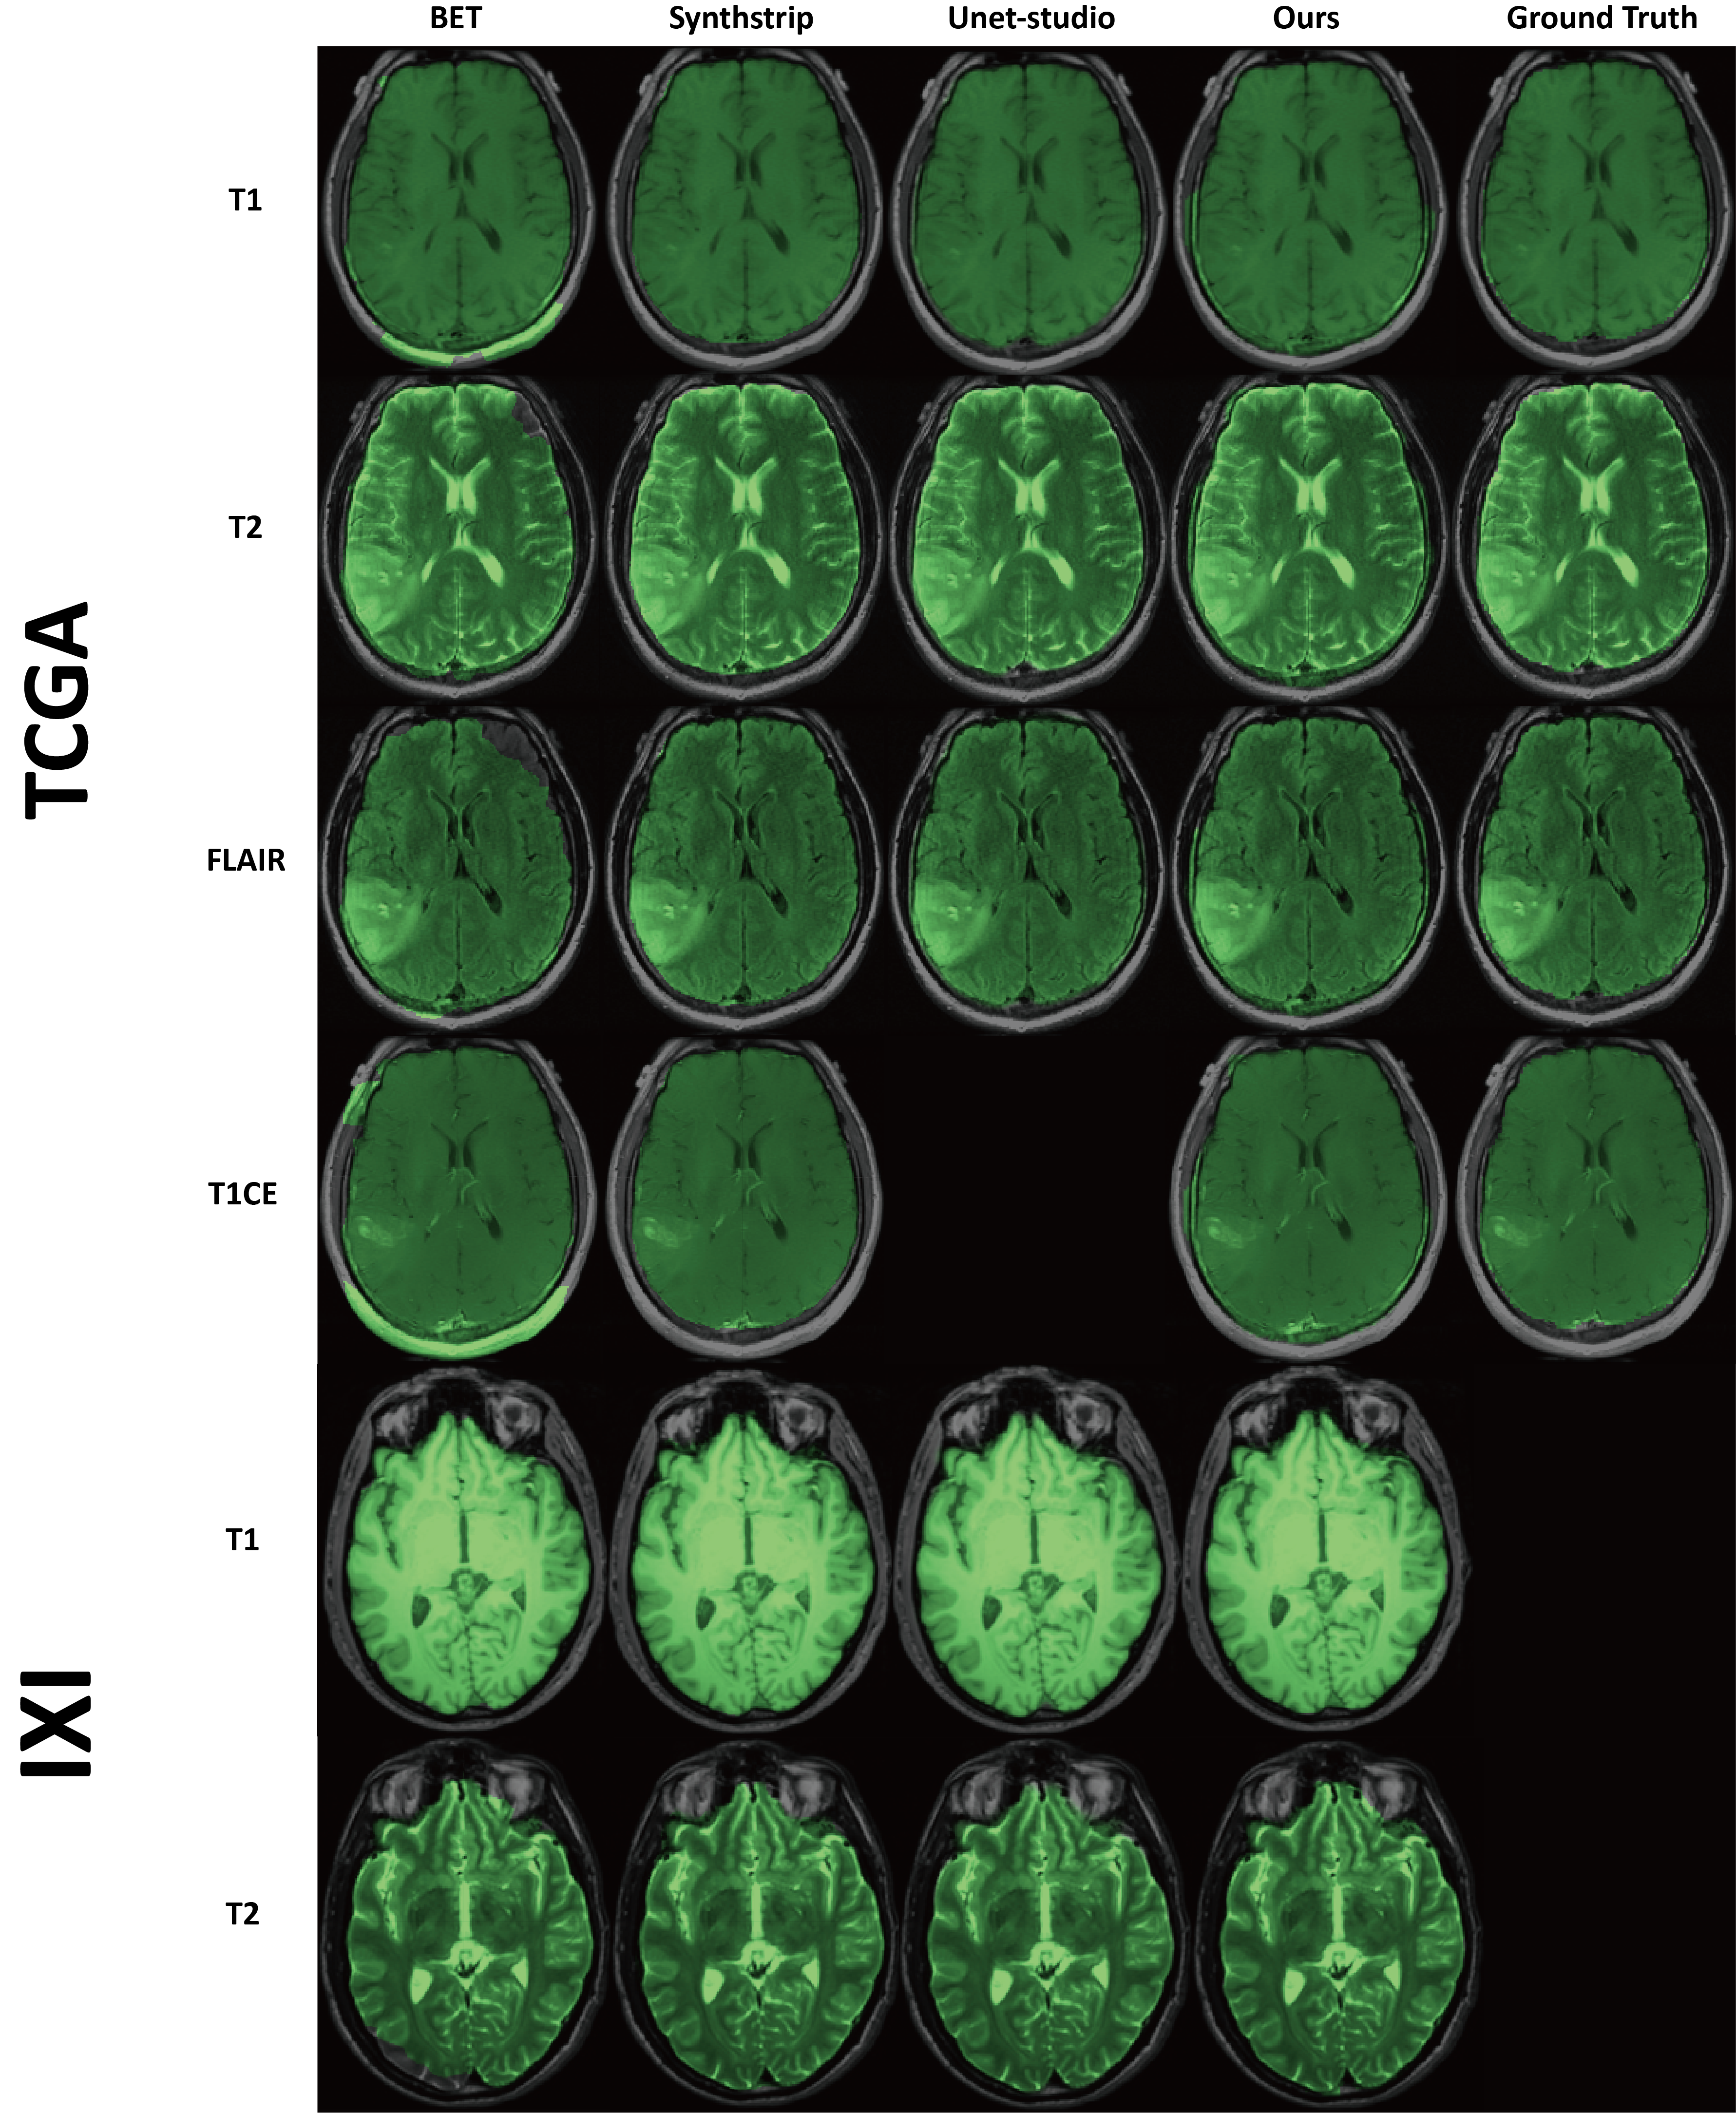

Refer to caption

Figure 4: The predicted mask of each method on multiple modalities of the TCGA (tumor) and the IXI (healthy) dataset. Ground truth is not provided for the IXI dataset.

Fig. 4, Fig. 5 and Fig. 6 illustrates our model’s capability on multiple type of images, including humans, control and pathological, marmosets, macaques and mice. Additional to the datasets from the previous section, we include IXI [12] for multi-modal human adult data, BORDEUX24 from the NHP dataset [43] for macaque brains, mouse and rat brains from the CAMRI dataset [15] and individually gathered mouse brains. More explanation on the mouse data can be found in the appendix. The figure exhibits robust results of the predicted brain mask on all cases, whereas compared methods have a noticeable failure on images beyond the method was tuned for.